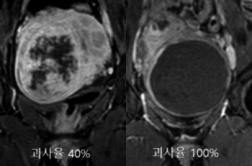

자궁근종 하이푸, 치료 잘 되었는지 궁금하세요?

자궁근종 하이푸, 치료 잘 되었는지 궁금하세요? 글 : 민트병원 자궁근종통합센터 김영선 원장/의학박사(영상의학과 전문의) 자궁근종 하이푸 치료 후 치료 방법을 평가하는 방법에는 여러가지가 있습니다. 가장 중요한 것은 …